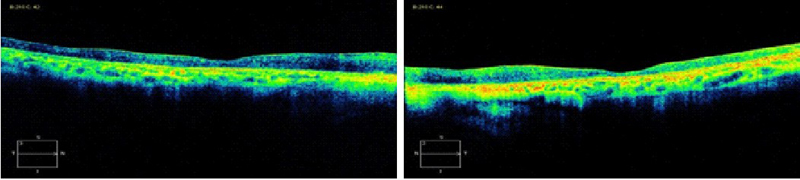

Coriorretinopatía en perdigonada (birdshot)

La coriorretinopatía tipo birdshot se caracteriza por lesiones coroideas bilaterales, simétricas y despigmentadas, vitreítis, vasculitis, edema macular e inflamación leve en la cámara anterior, siendo el edema macular la causa más importante de pérdida de visión. Los hallazgos de la OCT en los pacientes con inicio de la enfermedad incluyen un engrosamiento difuso de la retina que puede contribuir a la formación de EMC. La atrofia foveal difusa y la formación de MER se han observado en pacientes con largo tiempo de evolución de la enfermedad.

Con el uso de OCT, Monnet

et al31 reportaron, en una serie de casos, que el 31% de los pacientes presentaron edema macular, el 19% MER y el 4% fluido subretiniano. En este mismo estudio se describió la asociación con el engrosamiento o el adelgazamiento del grosor macular, la formación de membrana neovascular subretiniana fibrótica y el agujero macular. Los autores concluyen que la disrupción de la tercera banda, la unión entre los SI/SE de los fotorreceptores, observada por OCT, tenía una asociación más fuerte que cualquier otro parámetro. A favor, Forooghian

et al32 demostraron que la resolución de la tercera banda y de la arquitectura de la retina externa tras el tratamiento se asociaba a mejoría clínica.

Figura 22 y Figura 23. Paciente con coriorretinopatía en perdigonada o enfermedad de Birdhshot tras un episodio de actividad. En la OCT se evidencia la atrofia foveal tras la remisión de la actividad.